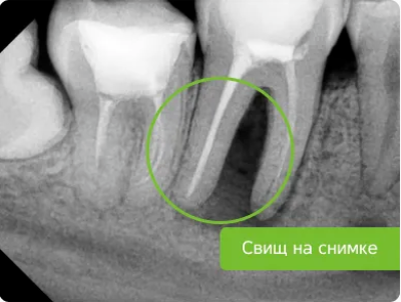

• исчезновение свищевого хода;

• наличие отека и образование свища;